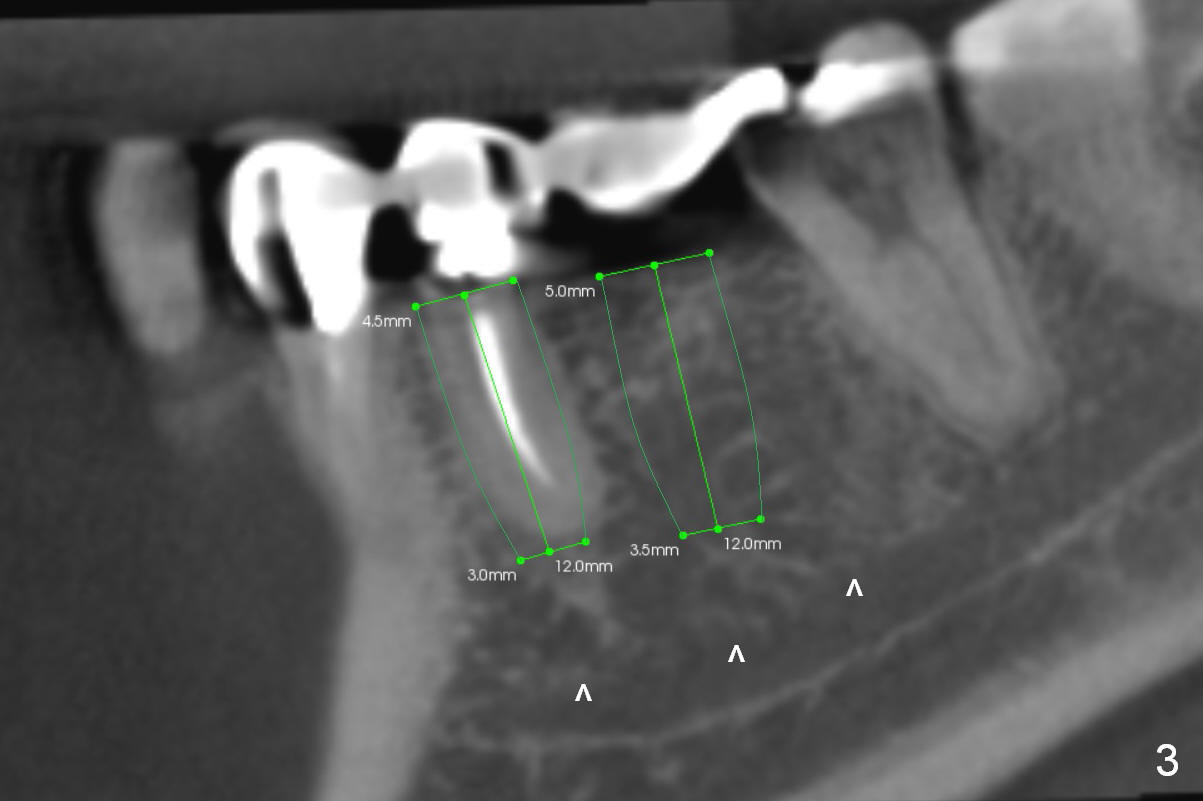

If it is the case, two implants will be placed at the sites of #29 and 30 (4.5x12 and 5x12 mm, respectively, Fig.3).